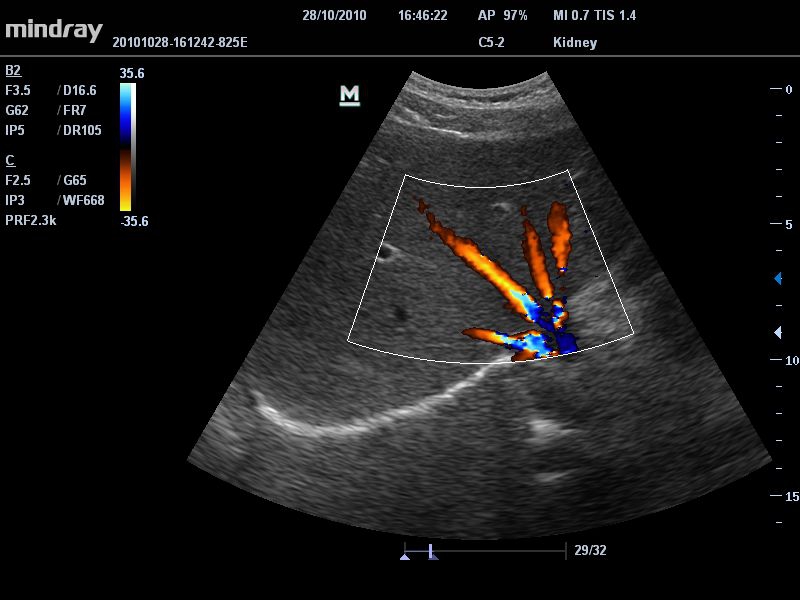

Mindray DC-T6

Ультразвуковая система Mindray DC-T6 – это инновационный аппарат для проведения высокого уровня диагностики с качественной визуализацией и широким спектром применения. Платформа рекомендована для использования в коммерчески многопрофильных медицинских учреждениях и государственных лечебных клиниках.

Цветовой допплер:

Да